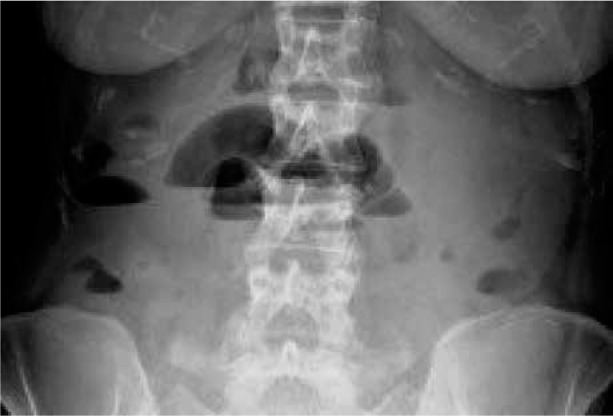

小肠梗阻(SBO)是一种严重的疾病,有明显的症状,如便秘、呕吐和腹胀。它通常是由公认的因素引起的。成像技术和微创手术的最新进展大大提高了我们准确选择手术干预患者和迅速识别常见SBO原因的能力。然而,认识到诊断罕见的SBO病因仍然是一项挑战,这一点至关重要。我们报告一个罕见的病例机械性肠梗阻由巨大的子宫肌瘤引起的44岁妇女。大子宫肌瘤可引起机械性小肠阻塞,虽然这不是常见的原因。诊断成像,特别是计算机断层扫描,在诊断和确定适当的管理计划中起着至关重要的作用。准确的监测和成像可以通过避免不必要的手术干预和降低发病率和死亡率来改善患者的预后。治疗方法包括内科和外科两种。这两种方法都被证明是有效的,如果药物治疗不成功,外科手术是最后的手段。这些手术方法的准确性和有效性已显示出良好的结果和显著的预后益处。识别和报告罕见的肠梗阻原因对于提高未来的认识和提高患者的预后是至关重要的。

Small bowel obstruction (SBO) is a serious condition with distinct symptoms such as constipation, vomiting, and abdominal distension. It is commonly caused by well-recognised factors. Recent advancements in imaging techniques and minimally invasive procedures have significantly improved our ability to accurately select patients for surgical intervention and promptly identify common SBO causes. Nonetheless, it is crucial to recognise that diagnosing rare SBO causes remains a challenge. We present a rare case of mechanical bowel obstruction caused by massive uterine fibroids in a 44-year-old woman. Large uterine fibroids can cause mechanical small intestine obstruction, although this is not a common cause. Diagnostic imaging, particularly computed tomography, plays a crucial role in diagnosing and determining appropriate management plans. Accurate monitoring and imaging can lead to improved patient outcomes by avoiding unnecessary surgical intervention and reducing morbidity and mortality rates. Treatment options include both medical and surgical methods. Both approaches have proven effective, with surgical procedures being the last resort if medical treatments are unsuccessful. The accuracy and efficacy of these surgical methods have shown promising results and significant prognostic benefits. It is critical to identify and report rare causes of bowel obstruction to improve future recognition and enhance patient outcomes.